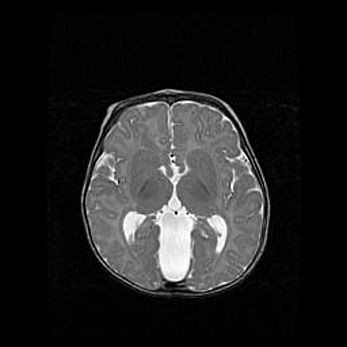

Церебральная ишемия II.

Возраст: 7 дней

Вес: 3350 г

Пол: женский

Окружность головы: 35 см

Срок гестации: 39 недель

Ишемия головного мозга – это состояние, которое развивается в ответ на кислородное голодание вследствие недостаточного мозгового кровообращения. У новорожденных она является следствием дефицита кислорода, что ведет к метаболическим расстройствам различной степени тяжести в тканях головного мозга, в том числе к развитию коагуляционных некрозов и гибели нейронов.